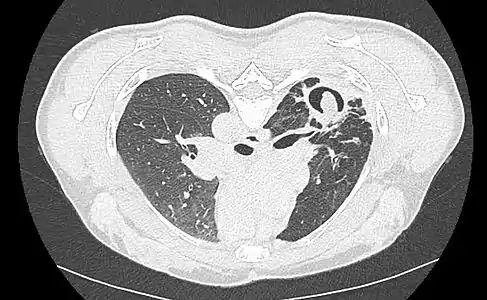

Sur la radiographie pulmonaire, un aspergillome simple apparaît comme un nodule dense, le plus souvent entouré d'un croissant aérique[11]. La radiographie seule ne suffit pas au diagnostic ; un scanner est recommandé[29]. Sur le scanner thoracique, le centre de la cavité est occupé par l'aspergillome[58]. La pseudo-tumeur bouge dans la cavité lorsque le patient change de position (signe de Monod)[58]. Dans l'aspergillome simple, il n'y a pas d'évolution entre les examens et la paroi de la cavité est le plus souvent fine[13]. Un aspergillome complexe[13] présente en revanche l'aspect d'une cavité (ou plusieurs) à parois épaisses, comportant en son centre une truffe aspergillaire. Il existe parfois un début de fibrose pulmonaire[59]. La plèvre adjacente a également un aspect fibrosé, et l'évolution radiologique est lente, mais toujours vers l'aggravation[13]. Un halo en verre dépoli peut également entourer les lésions[45].

Aspect scannographique typique d'un aspergillome développé dans une caverne tuberculeuse.

Le changement de position modifie la position du grelot aspergillaire dans la cavité (signe de Monod).

Le diagnostic radiologique seul n'est cependant pas adapté, d'autres lésions pouvant avoir une présentation similaire (cancer pulmonaire excavé[60],[14] notamment, mais aussi abcès pulmonaire et kyste hydatique[14]). L'injection de produit de contraste iodé, dans le but de mieux visualiser les vaisseaux, permet de dépister un anévrysme de Rasmussen[61], une dilatation pseudo-anévrysmale de l'artère pulmonaire au voisinage d'une cavité intrapulmonaire à risque de rupture, qui entraîne alors une hémoptysie massive souvent fatale[62].